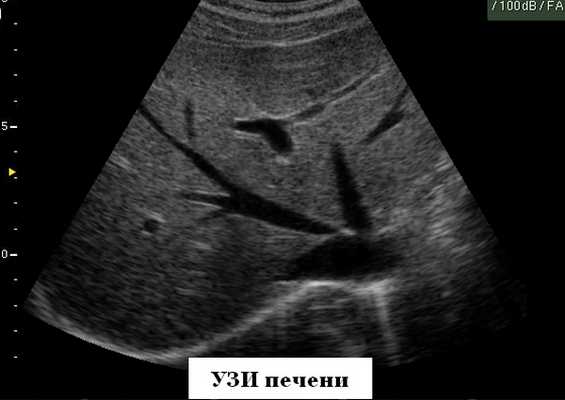

Печень

Ультразвуковое исследование печени можно проводить в любое время без предварительной подготовки. Обследование проводится, как правило, в трех плоскостях (продольной, поперечной и косой) со стороны правого подреберья и эпигастрия. При этом необходимо оценить расположение, форму, контуры, размеры, структуру и эхогенность паренхимы, сосудистый рисунок в целом и конкретные сосуды, протоковую систему, влияние окружающих органов на состояние изображения печени. Точность диагностики выявляемых изменений возрастает при динамическом наблюдении (схема 3).

В норме большая часть печени располагается справа от позвоночника, а меньшая - слева от него и доходит до левой парастернальной линии. Контуры печени ровные, она имеет четкое очертание, капсула хорошо просматривается в виде гиперэхогенной структуры, окружающей ее паренхиму (за исключением участков, прилежащих к диафрагме, где капсула не дифференцируется от последней). В норме нижний край печени не выступает из-под реберной дуги. Общепринятыми являются измерение косого вертикального размера правой доли (не превышает 13-15 см) и толщины левой доли (до 5 см). Структура неизмененной печени представлена мелкозернистым изображением, состоящим из множества мелких точечных и линейных структур, равномерно расположенных по всей площади полученного среза. По эхогенности паренхима нормальной печени сопоставима или несколько выше эхогенности коркового вещества почки (при отсутствии ее патологии). Эхография позволяет дифференцировать различные трубчатые структуры, находящиеся в печени.

Отличительным признаком печеночных вен является их радиальное расположение (от периферии к центру), "отсутствие" стенок, возможность проследить ход мелких ветвей (до 1 мм в диаметре) до периферии органа. Портальная вена образуется в результате слияния верхнебрыжеечной и селезеночной вен. Лучше всего она видна при косом сканировании через правое подреберье и визуализи-руется в виде трубчатой структуры, имеющей четкие стенки. Ее можно проследить от места образования до впадения в ворота печени, где она разделяется на левую и правую ветви. В норме диаметр воротной вены не превышает 13-15 мм. Печеночная артерия визуализируется в области ворот печени как трубчатая структура небольшого диаметра (до 4-6 мм) с высокоэхогенными стенками. Внутрипеченочные желчные протоки в норме могут быть визуализированы только начиная с долевых. Они также имеют высокоэхогенные стенки и малый диаметр (не более 1 мм).

Результаты исследований

Рис. 1. Эхографическая картина нормальных левой и правой долей печени.